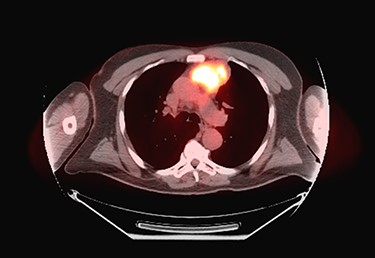

Sixty-three-year-old male was with the history of diabetes and hypertension who presented with 2 days of new onset, intermittent and non-pleuritic left-sided chest pain, with a few months of new onset exertional dyspnea. Chest X-ray showed a convex shaped mass at the left hilum. Chest CT angiography revealed a 5.6 × 7.1 × 5.4 cm hypodense mass in the anterior mediastinum involving the adjacent anterior medial left upper lobe, and adjacent mildly enlarged aorticopulmonary window lymph nodes (Fig. 1). PET scan demonstrated a hypermetabolic anterior mediastinal mass adjacent to medial left upper lobe highly suggestive of malignancy (Fig. 2). Ultrasound-guided core needle biopsy showed nests of small cells with peripheral palisading and focal abrupt transition to squamous cell, consistent with basaloid carcinoma of thymic gland. Immunostainings of the tumor cells were positive for cytokeratin AE1/AE3, cytokeratin CK904, p63 and p40.

Chest CT angiography revealed a 5.6 × 7.1 × 5.4 cm hypodense mass in the anterior mediastinum involving the adjacent anterior medial left upper lobe.